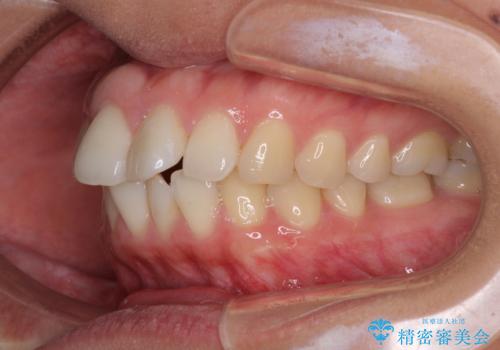

- 前歯の出っ歯と口元の閉じにくさを気にして来院された患者様です。

口元を積極的に引っ込めるために、上下左右の小臼歯4本を抜歯することとしました。

4本の歯を抜歯したことで、飛び出していた口元が引っ込み、横顔が大きく改善されました。

咬み合わせが悪化することのないようにスペースを閉じていくことができ、比較的スムーズに治療を進めることができました。